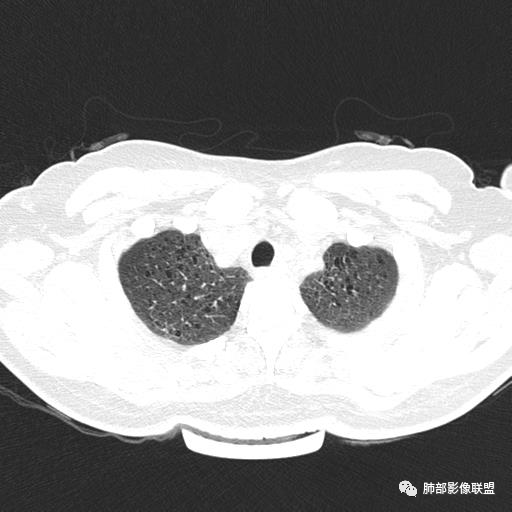

中年女性,不吸烟

双肺弥漫囊腔,累及肋膈角,囊腔形态相对规则单一。

符合LAM

CT平扫示双肺弥漫分布大小不等囊状薄壁透光区,无内、中、外带分布差异,间质稍示增厚。拟LAM

中年女性育龄期妇女,咳嗽气喘,无吸烟史,有苯吸入史。影像:双肺弥漫均匀小囊腔,无明显分布优势,囊腔形态欠规则,壁薄,部分囊腔边缘血管征,伴双肺弥漫磨玻璃影,无结节,考虑lam,鉴别苯中毒肺损伤,囊腔多有分布优势,小叶中心分布为主,形态规整等

女,46,活动性气喘1年。苯吸入史半年。胸部CT:两肺弥漫囊腔,上至肺尖,下至肋膈角,形态类似小囊腔。考虑:LAM,鉴别LIP,BHD,PLCH等。

双肺弥漫大小不一薄壁含气囊腔,囊间肺组织正常,正常肺背景,肺尖肺底受累;青年女性,气喘,支持LAM

双肺多发大小相近的囊状影,分布趋势趋于一致,中年女性,考虑LAM。部分囊内见血管及分隔影,小叶中心性肺气肿代排

CT表现:双肺弥漫大小不等的薄壁囊腔,囊壁<2mm,外形规则,血管影多位于囊腔周围,囊腔之间肺组织正常,随着疾病进展到晚期,囊腔变大、增多,不可胜数,囊腔可融合成较大的囊,与肺气肿相似,形成间质性肺纤维化。部分病例可出现结节影。